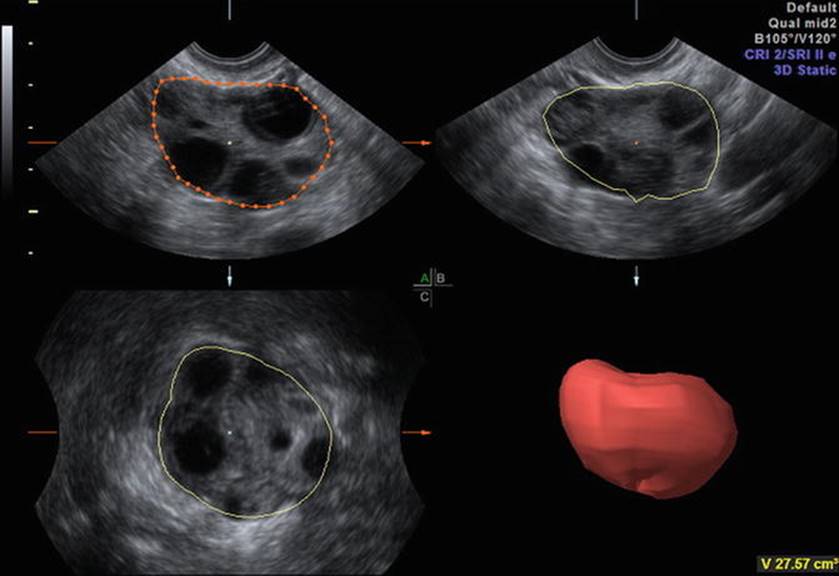

Fig. 2.2

Ovarian volume

The optimum cut-off value for hyper-response of AFC is ≥14 with a sensitivity of 82 % and specificity 89 % to predict ovarian hyperstimulation syndrome (OHSS). The ovarian volume also correlates with the number of growing follicles, but not with the number of oocytes retrieved [2]. It was also observed that women with small ovaries with a volume of less than 3 cm3 have a very high cancellation rate of in vitro fertilization (IVF) [3]. 3-dimensional ultrasound allows more precise calculation of ovarian and stromal volumes (Fig. 2.2). However, yet again, the predictive value for pregnancy by measuring the ovarian and stromal volume is limited (1.0–1.4) [4, 5].